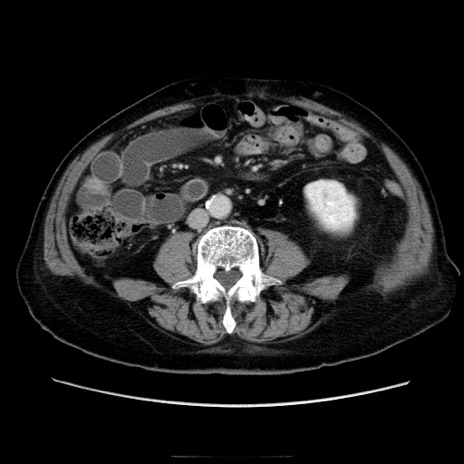

症例21(横断像)

【症例】70歳代男性

【現病歴】肝硬変・肝細胞癌にてかかりつけの方。約9時間前に食後より腹痛出現。症状が徐々に増悪し、嘔吐出現したため来院。

【既往歴】肝硬変、肝細胞癌(RFA、TACE後)

【身体所見】意識清明、表情苦悶様、BT 36℃、BP 129/78mmHg、P 88bpm、SpO2 97%(RA)、右上腹部から心窩部にかけて圧痛あり、反跳痛なし、筋性防御あり。

【データ】WBC 5800、CRP 0.16